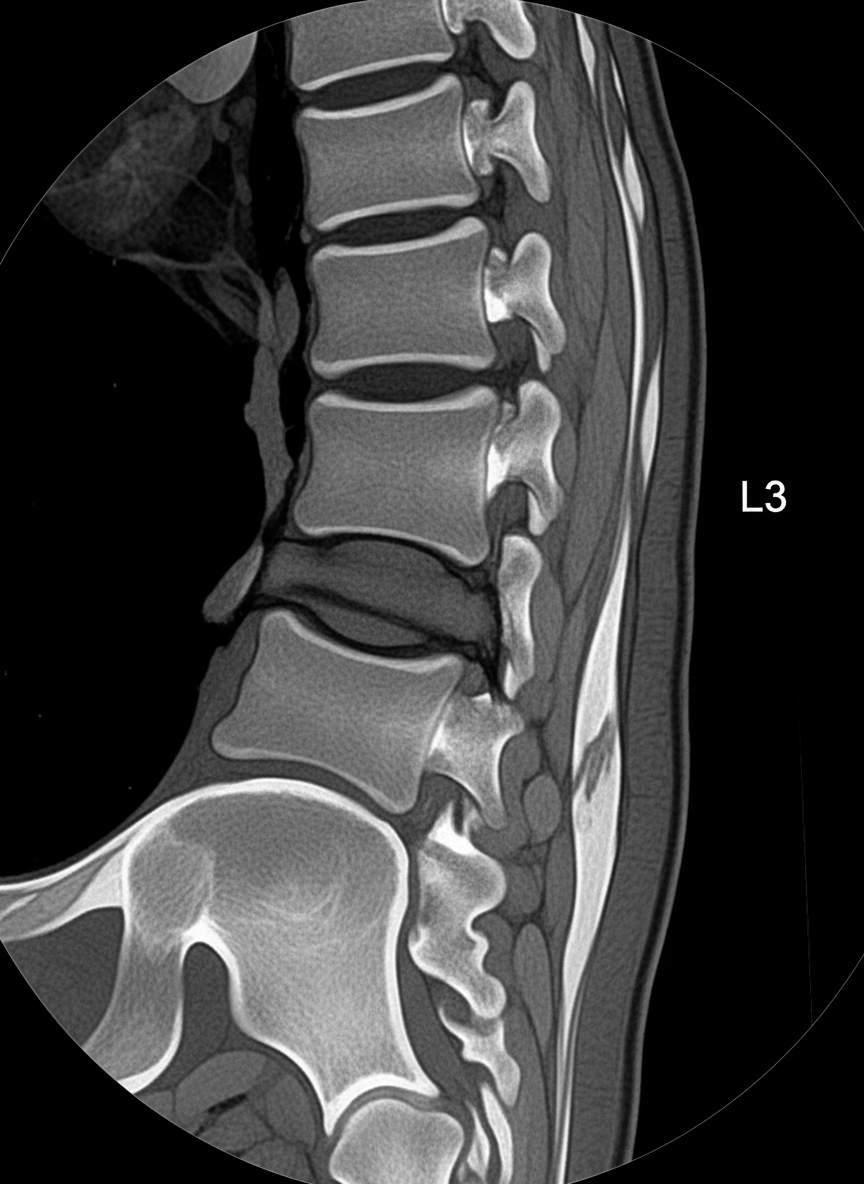

신장 질환: 소리 없이 찾아오는 위험 신호

신장! 우리 몸의 콩팥이죠.

왼쪽 신장은 왼쪽 옆구리 뒤쪽에

자리 잡고 있는데요,

이 신장에 문제가 생겨도

왼쪽 옆구리 통증이 나타날 수 있어요.

앞서 말씀드린 요로결석처럼

갑작스럽고 극심한 통증보다는

은은하고 지속적인 통증으로 나타나는 경우가 많아

자칫하면 대수롭지 않게 여기기 쉬워요.

그래서 '소리 없는 장기'라고 불리기도 하죠.

대표적인 신장 질환으로는

신우신염(신장 감염)이나 신장 낭종,

수신증(신장에 물이 차는 현상) 등이 있어요.

신우신염의 경우,

옆구리 통증과 함께 발열, 오한,

소변 볼 때 통증이 있거나

탁한 소변이 나오는 증상이 나타나기도 해요.

만약 신장에 종양이나 물혹 같은

다른 문제가 있다면,

초기에는 통증이 없을 수 있지만

병이 진행될수록 묵직한 통증을 유발할 수 있고요.